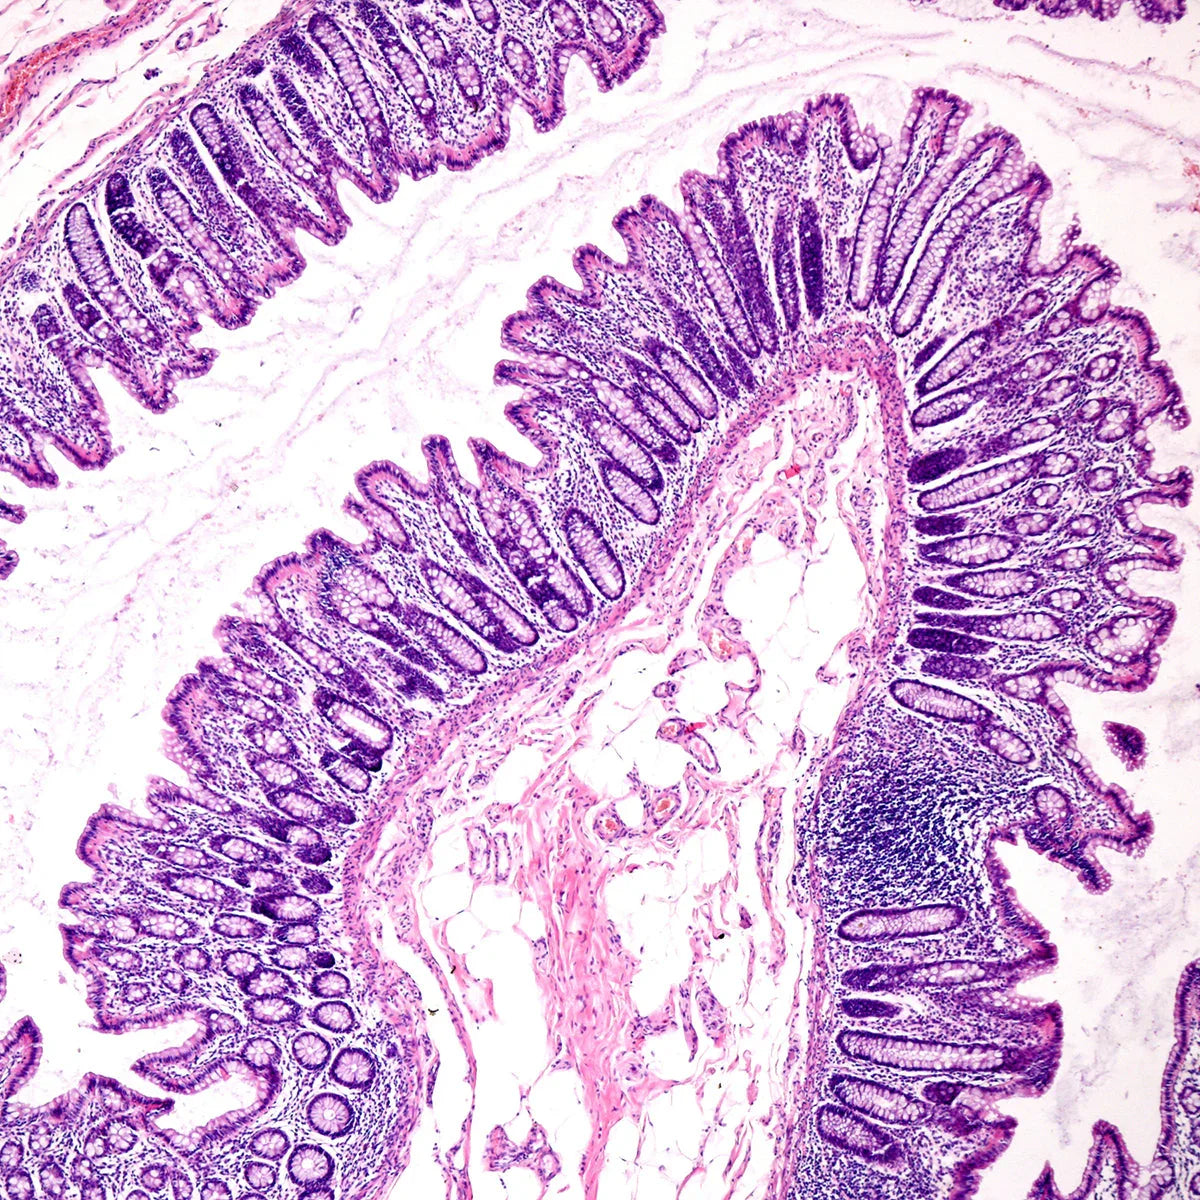

Sindrom prepustnega črevesja je pogosto povezan z neravnovesjem črevesne flore. Zmanjšanje koristnih bakterij in povečanje škodljivih bakterij lahko prispevata k povečani prepustnosti črevesja. Dodajanje probiotikov pomaga obnoviti ravnovesje črevesne flore, kar je bistveno za ohranjanje zdravja in pravilnega delovanja črevesja.

Sindrom prepustnega črevesja je skoraj vedno spremljan s kroničnim vnetjem, saj snovi, ki iz črevesja prehajajo v krvni obtok, sprožijo imunske odzive. Probiotiki lahko pomagajo zmanjšati ta vnetni odziv z modulacijo imunskih funkcij in podporo protivnetnim procesom. To je še posebej pomembno za celjenje črevesne stene in zmanjšanje splošnih vnetnih stanj.

Probiotiki prav tako krepijo črevesno pregrado in preprečujejo prehod škodljivih snovi ter patogenov. Ohranjanje celovitosti črevesne stene je ključno za ustrezno delovanje imunskega sistema, saj črevesje deluje kot filter, ki nadzoruje, katere snovi vstopajo v krvni obtok.